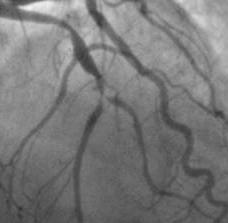

Estimation of the length of that portion of the stenosis that has ≥50% reduction in luminal diameter in the projection where the lesion appears to be the longest. (In case of a bifurcation lesion at least one of the branches has a lesion length of >20mm).